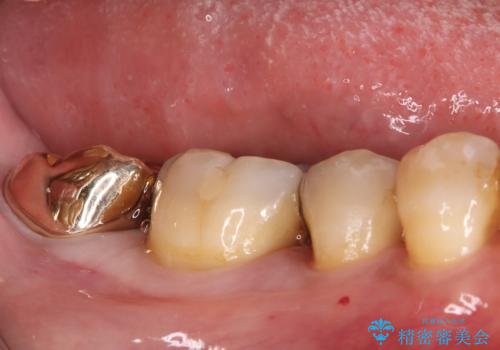

根の病変を精密治療で改善。再発を防ぐ根管治療とオールセラミッククラウン

担当医 河口智英